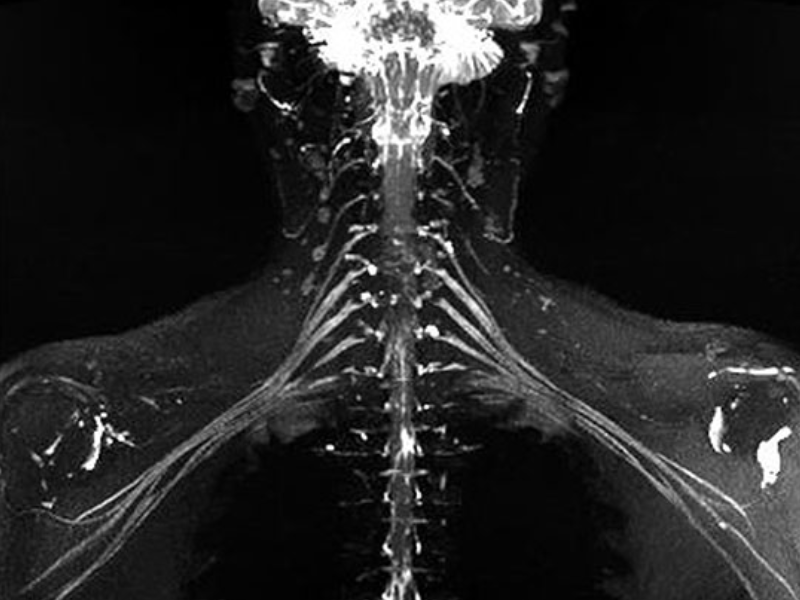

T1W FSE C-Spine